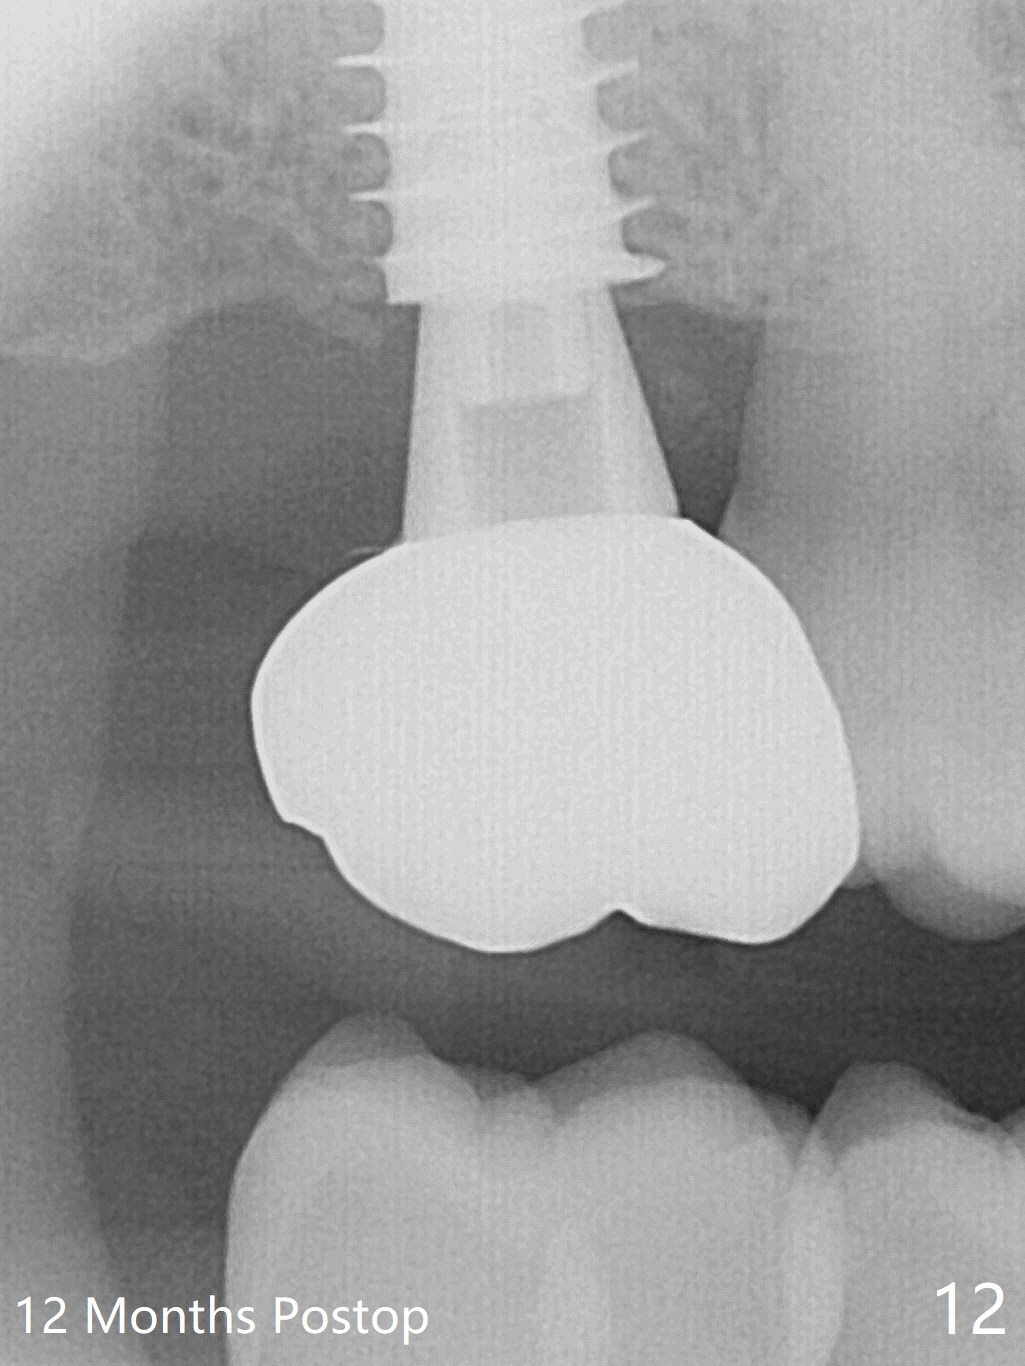

The implant is stable with the healing abutment 8 months postop (Fig.11). There is definitive sign of osteointegration 12 months postop (3 months post cementation, Fig.12). The patient is pleased to have the implant for 1 year 7.5 months post cementation (Fig.13).